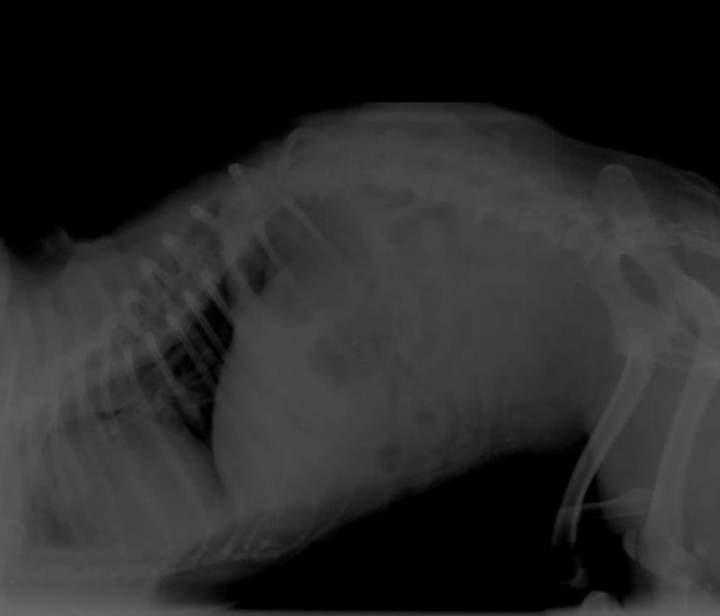

Un soir de garde nous a été amené un chien de type Carlin, restant immobile au sol, couché sur le flanc. Il présentait "une bosse sur le ventre".

L'examen clinique a montré une dilatation gazeuse en partie avant de l'abdomen. Une radiographie a été réalisée afin de confirmer une dilatation- torsion de l'estomac. Cet examen a confirmé cette hypothèse.

En cas de dilatation et torsion éventuelle de l'estomac, on observe en arrière du diaphragme une (en cas de dilatation) ou deux (en cas de torsion) zones apparaissant plus noire donc moins opaque(s) aux rayons X, contenant donc de l'air en grande quantité.